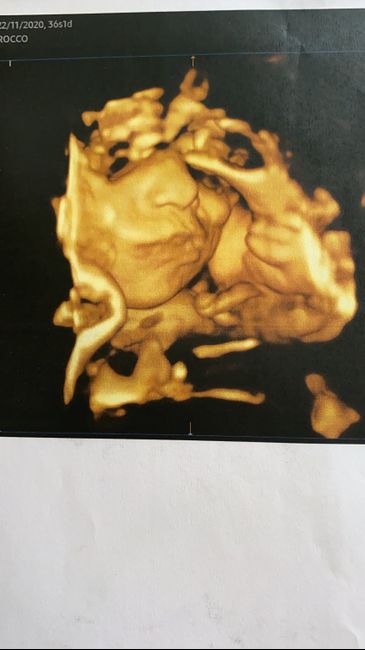

Ciao fede abbastanza bene stamattina visita a 36+1 va tutto bene i parametri sono buoni solo che Ale ha rallentato un po’ la crescita per i miei problemi di trombofilia e utero fibromiatoso io mi sono un po’ spaventata ma il dottore ha detto che lui sta benissimo flussimetria perfetta battito perfetto e flusso di sangue al cervello perfetto avendo io questi problemi il bimbo si adatta cesareo programmato per il 14 agosto peso stimato 2800/2900 -12 giorni e sarà tra le mie braccia finalmente vi lascio una fotina anche se ha sempre le manine davanti al viso 😅😅Future mamme Agosto 2021! 1